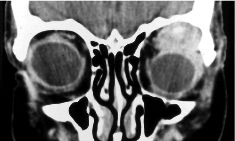

Computed tomography (CT) and magnetic resonance imaging (MRI) may demonstrate an ovoid soft tissue mass in the superotemporal orbit with irregular margins and possible bony erosion even while the tumor is small. Focal calcifications may also be present (Fig. 2A, 2B).

Fig. 2: (A) Coronal CT of an adenoid cystic carcinoma with irregular mass arising from the left anterior superotemporal orbit with possible focal calcification. (B) Axial CT of an adenoid cystic carcinoma invading the left lateral orbital wall (arrow).